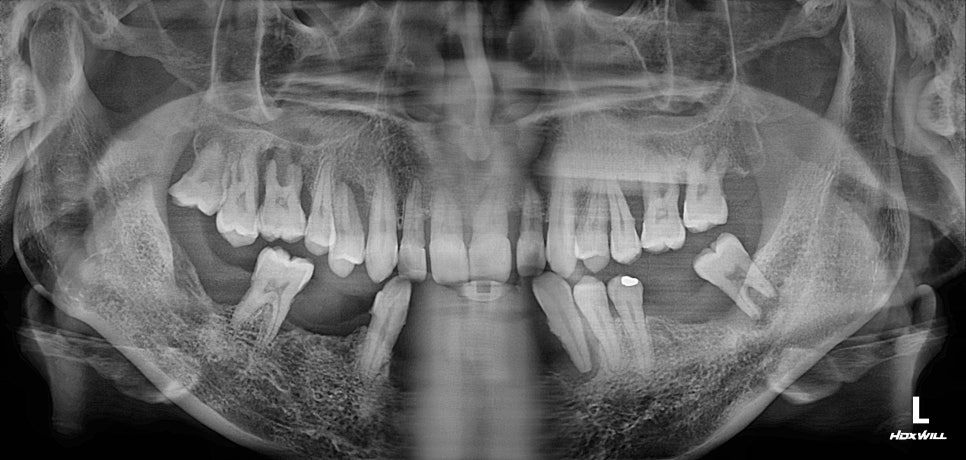

40대 남성 치아 대부분이 흔들리고 안좋은 상태 두려움과 걱정으로 치료를 미루시다 지인의 추천으로 큰 맘 먹고 오셨습니다. 살릴 수 있을만한 치아가 거의 없습니다. 전체 임플란트를 해도 되는 케이스입니다. 그런데 40대의 나이에 내 치아 없이 전체임플란트를 한다는 것은 심리적 충격이 상당합니다. ...

치아 대부분이 흔들리고 안좋은 상태

두려움과 걱정으로 치료를 미루시다

지인의 추천으로 큰 맘 먹고 오셨습니다.

살릴 수 있을만한 치아가 거의 없습니다.

전체 임플란트를 해도 되는 케이스입니다.

위 앞니도 잇몸뼈가 좋지 않아서

벌어지고 염증이 있는 상태입니다.